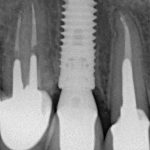

Например, однажды в блоге я показывал вот эту работу, но не показывал снимки. Смотрите сами:

вот фотография и снимок сразу после имплантации:

вот снимки через полгода после протезирования:

а вот — примерно через два года:

Как видите, ни по фотографиям, ни по рентгеновским снимкам никаких серьезных изменений нет. А это значит, что мы получили хороший и, главное, ПРЕДСКАЗУЕМЫЙ результат. И контролировать его позволяют профилактические осмотры и долгосрочное наблюдение — именно это является основой гарантии, предоставляемой на имплантологическое лечение в нашей клинике.